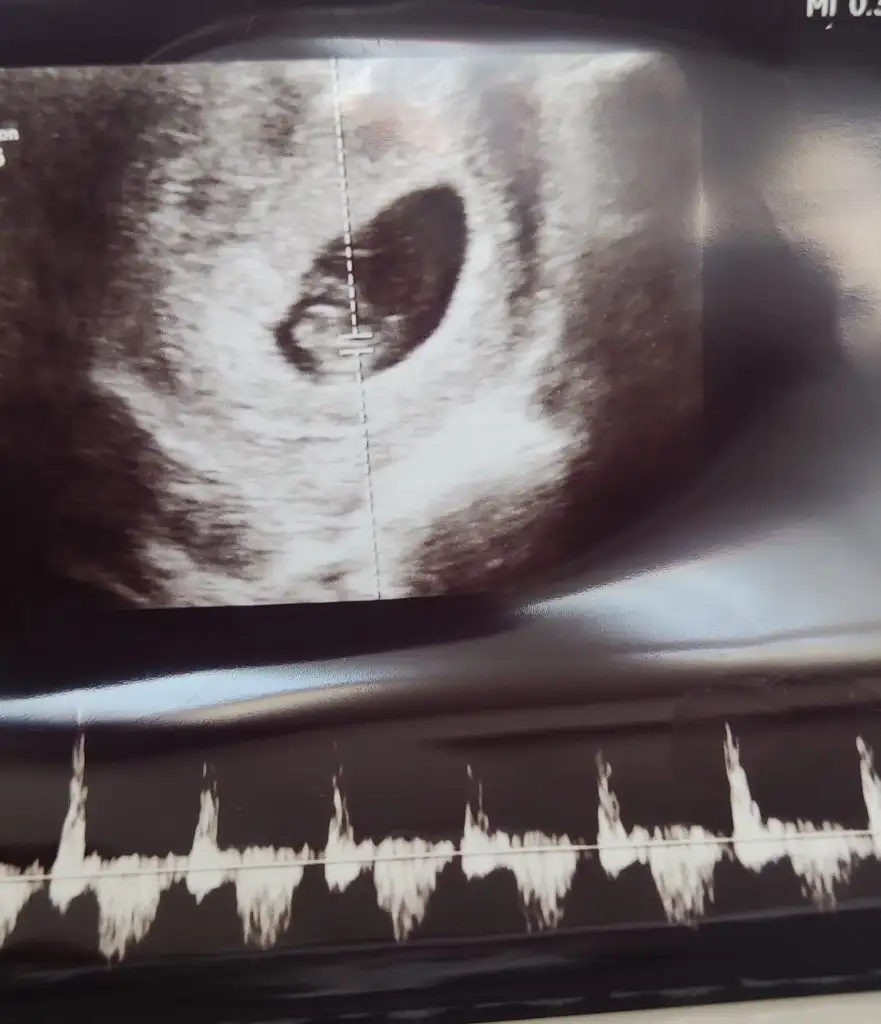

Mrb rica etsem banada yorum yapabilirmisiniz 🤲

Eklentiler

• Screenshot_2024-06-27-10-22-14-635_com.miui.videoplayer.webp

Screenshot_2024-06-27-10-22-14-635_com.miui.videoplayer.webp

12,1 KB · Görüntüleme: 23